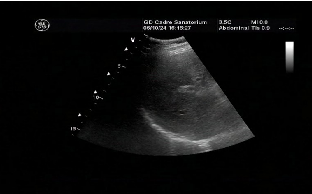

6. 定期检查。改变不良生活方式,半年定期复查B超、肝功能。即使是中度和重度脂肪肝,改善生活方式仍然是基础且重要的治疗手段。即使已经发展到肝硬化阶段,通过积极的治疗和生活方式的调整,也可以延缓疾病的进程。